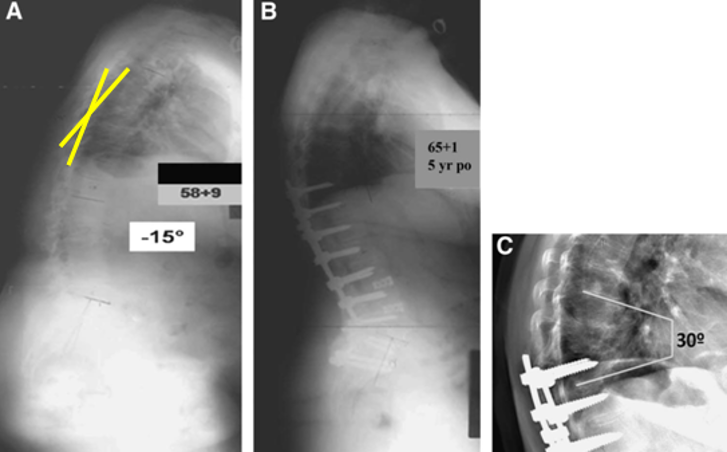

(3)肋骨固定

T10骨盆固定,出现交界性后凸

行翻修手术:T9/10SP截骨,延长到T4固定,预防性双侧肋骨固定(VEPTR)

图32-33 肋骨固定